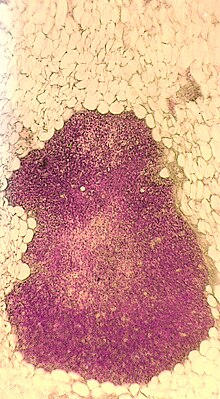

Im Gegensatz zu den übrigen lymphatischen Organen, die ausschließlich aus dem Mesoderm hervorgehen, entwickelt sich der Thymus aus dem Meso-, dem Ento- und dem Ektoderm und wird daher als lymphoepitheliales Organ bezeichnet. Histologisch lassen sich im Thymus Läppchen (Lobuli thymici) mit Rinde und Mark unterscheiden. Besonders im Thymusmark befinden sich beim Menschen und den meisten anderen Wirbeltieren die für das lymphatische Gewebe des Thymus typischen Hassall-Körperchen.